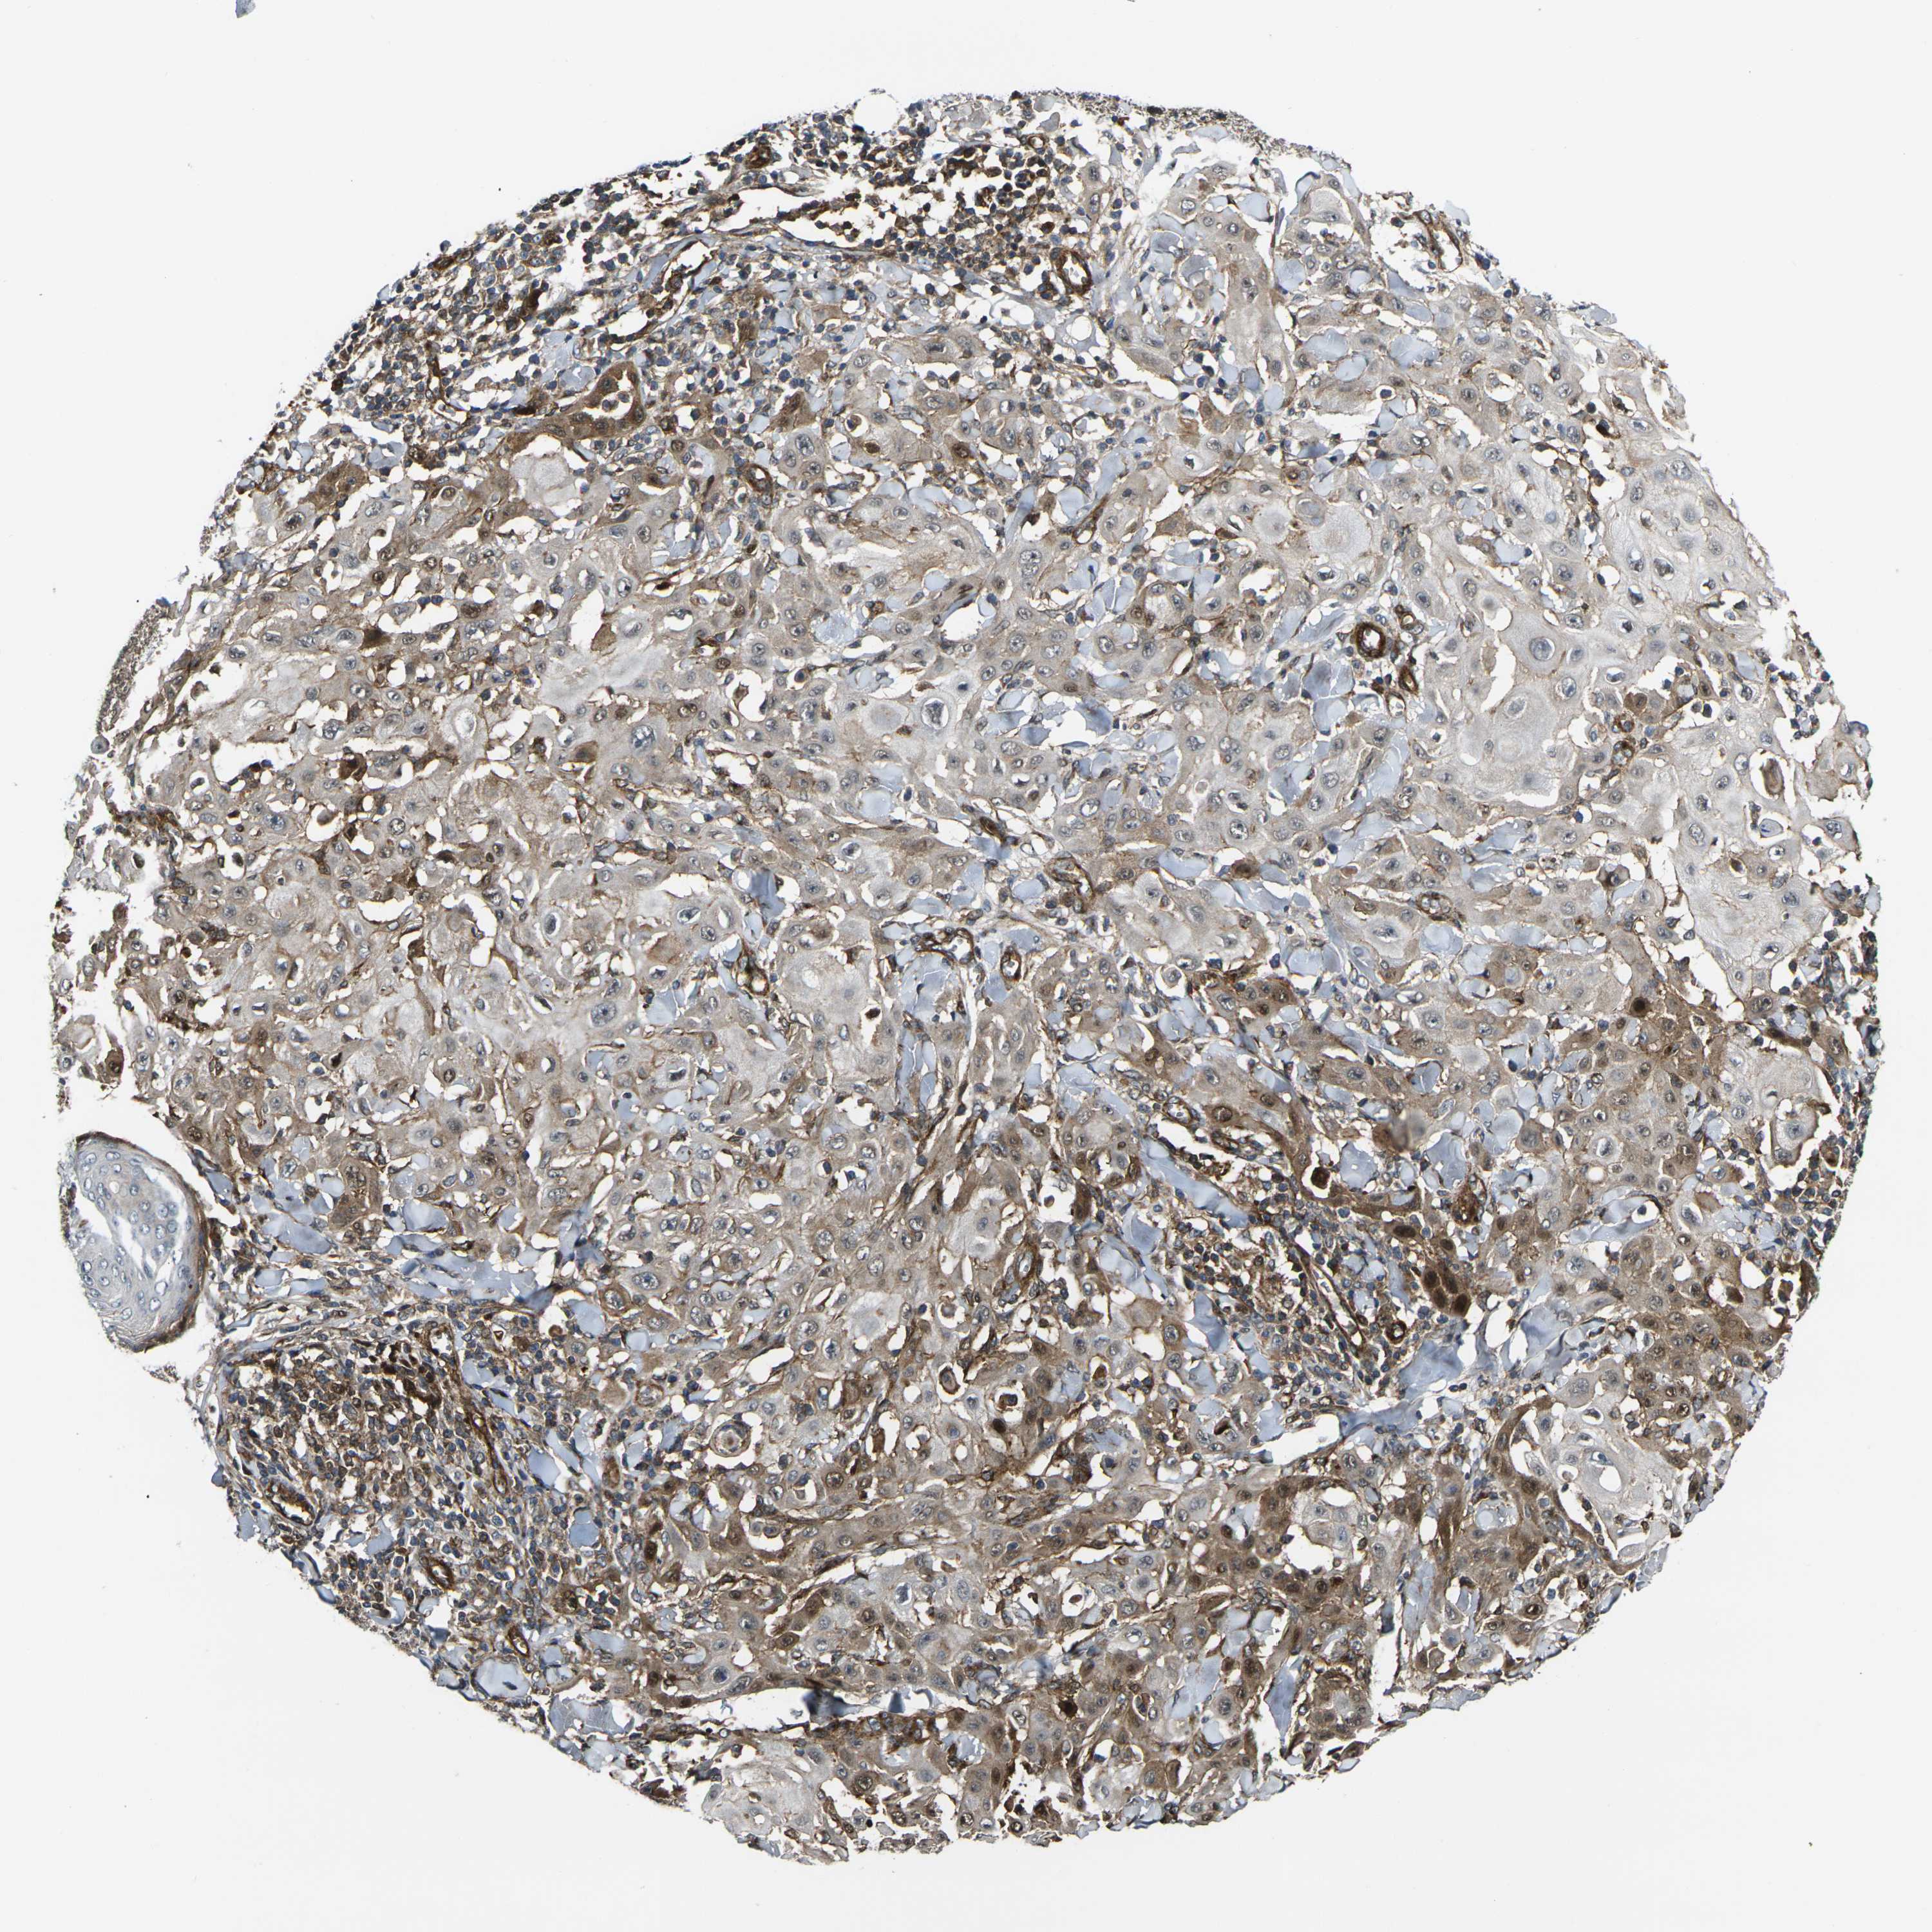

SKIN CANCER - Protein expressioni

A mouse-over function shows sample information and annotation data. Click on an image to view it in a full screen mode. Samples can be filtered based on level of antibody staining by selecting one or several of the following categories: high, medium, low and not detected. The assay and annotation is described here.

Each image is clickable and will lead to virtual microscopy that enables deeper exploration of all samples and also displays staining intensity scores, fraction scores and subcellular localization as well as patient and tissue information for each sample.

Antibody HPA001490

Basal cell carcinoma